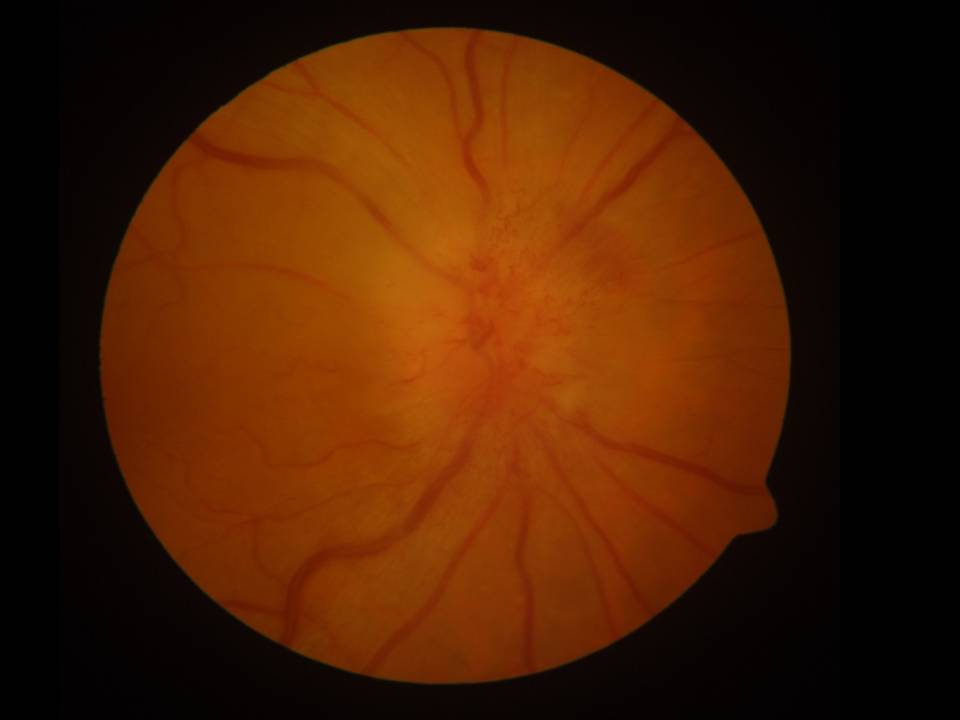

Ein 82-jähriger Mann berichtet über eine plötzlich aufgetretene und schmerzlose Sehverschlechterung auf dem rechten Auge, die er seit 2 Tagen bemerke.

Die Sehschärfe beträgt aktuell 1/50, zuvor konnte er mit dem Auge lesen. Im Gesichtsfeld sehen sie einen horizontal betonten Ausfall. Das andere Auge zeigt keine krankhaften Auffälligkeiten.